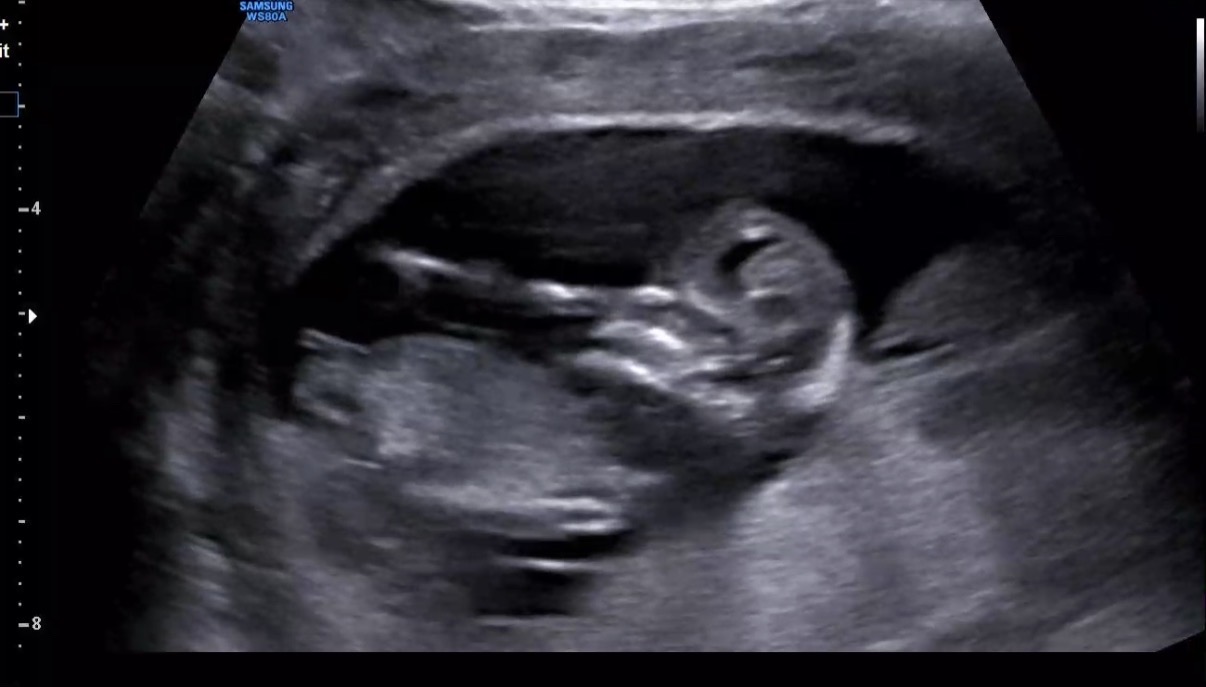

따끈따끈 12주 0일 각도법 투표 부탁드려용!🙏🏻💛

다들 어떤 것 같으세요? 병원에서는 안 보인다고 바로 딱 자르시더라구요ㅠ 한번 봐주시고 의견 주세용 ㅎㅎ